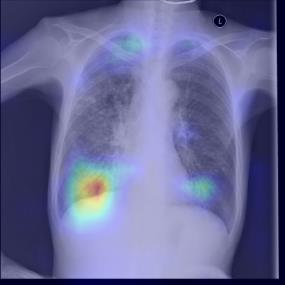

Chest X-ray (CXR) is the most typical diagnostic X-ray examination for screening various thoracic diseases. Automatically localizing lesions from CXR is promising for alleviating radiologists' reading burden. However, CXR datasets are often with massive image-level annotations and scarce lesion-level annotations, and more often, without annotations. Thus far, unifying different supervision granularities to develop thoracic disease detection algorithms has not been comprehensively addressed. In this paper, we present OXnet, the first deep omni-supervised thoracic disease detection network to our best knowledge that uses as much available supervision as possible for CXR diagnosis. We first introduce supervised learning via a one-stage detection model. Then, we inject a global classification head to the detection model and propose dual attention alignment to guide the global gradient to the local detection branch, which enables learning lesion detection from image-level annotations. We also impose intra-class compactness and inter-class separability with global prototype alignment to further enhance the global information learning. Moreover, we leverage a soft focal loss to distill the soft pseudo-labels of unlabeled data generated by a teacher model. Extensive experiments on a large-scale chest X-ray dataset show the proposed OXnet outperforms competitive methods with significant margins. Further, we investigate omni-supervision under various annotation granularities and corroborate OXnet is a promising choice to mitigate the plight of annotation shortage for medical image diagnosis.